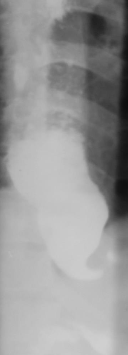

Achalazia cardiei